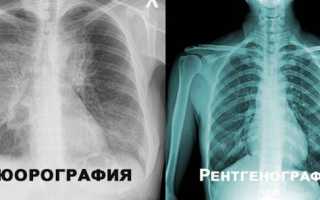

Многие люди считают, что рентген грудной клетки с флюорографией являются одинаковыми обследованиями. Однако они отличаются друг от друга техникой проведения, информативностью и назначениями. При этом только специалист назначает пациенту конкретный вид обследования, учитывая имеющиеся симптомы с жалобами.

Рентген грудной клетки, в отличие от флюорографии, считается более качественным диагностическим способом, потому что имеет высокую разрешительную способность. Такое обследование осуществляют, если есть подозрение на легочные патологии, флюорографию – в целях профилактики. При этом разница между 2 диагностиками будет заключаться в способности различать тени.

Благодаря рентгену допустимо увидеть тени примерно 2 мм, флюорографии – около 5 мм. В ходе выполнения рентгенографии луч проникает сквозь исследуемые ткани и выдает на экране выбранную область снимка.

- Разница между флюорографическим и рентгенографическим исследованиями заключается в разрешающей способности. Первая процедура способна не отобразить маленькие инфильтративные очаги и иные поражения легочных тканей.

Для понимания, что результативнее и лучше, требуется сравнить флюорографический и рентгенографический снимки. В первом случае не нужны затраты и много времени. Вторая процедура более информативная, потому что позволяет получить четкие и большие негативные изображения.